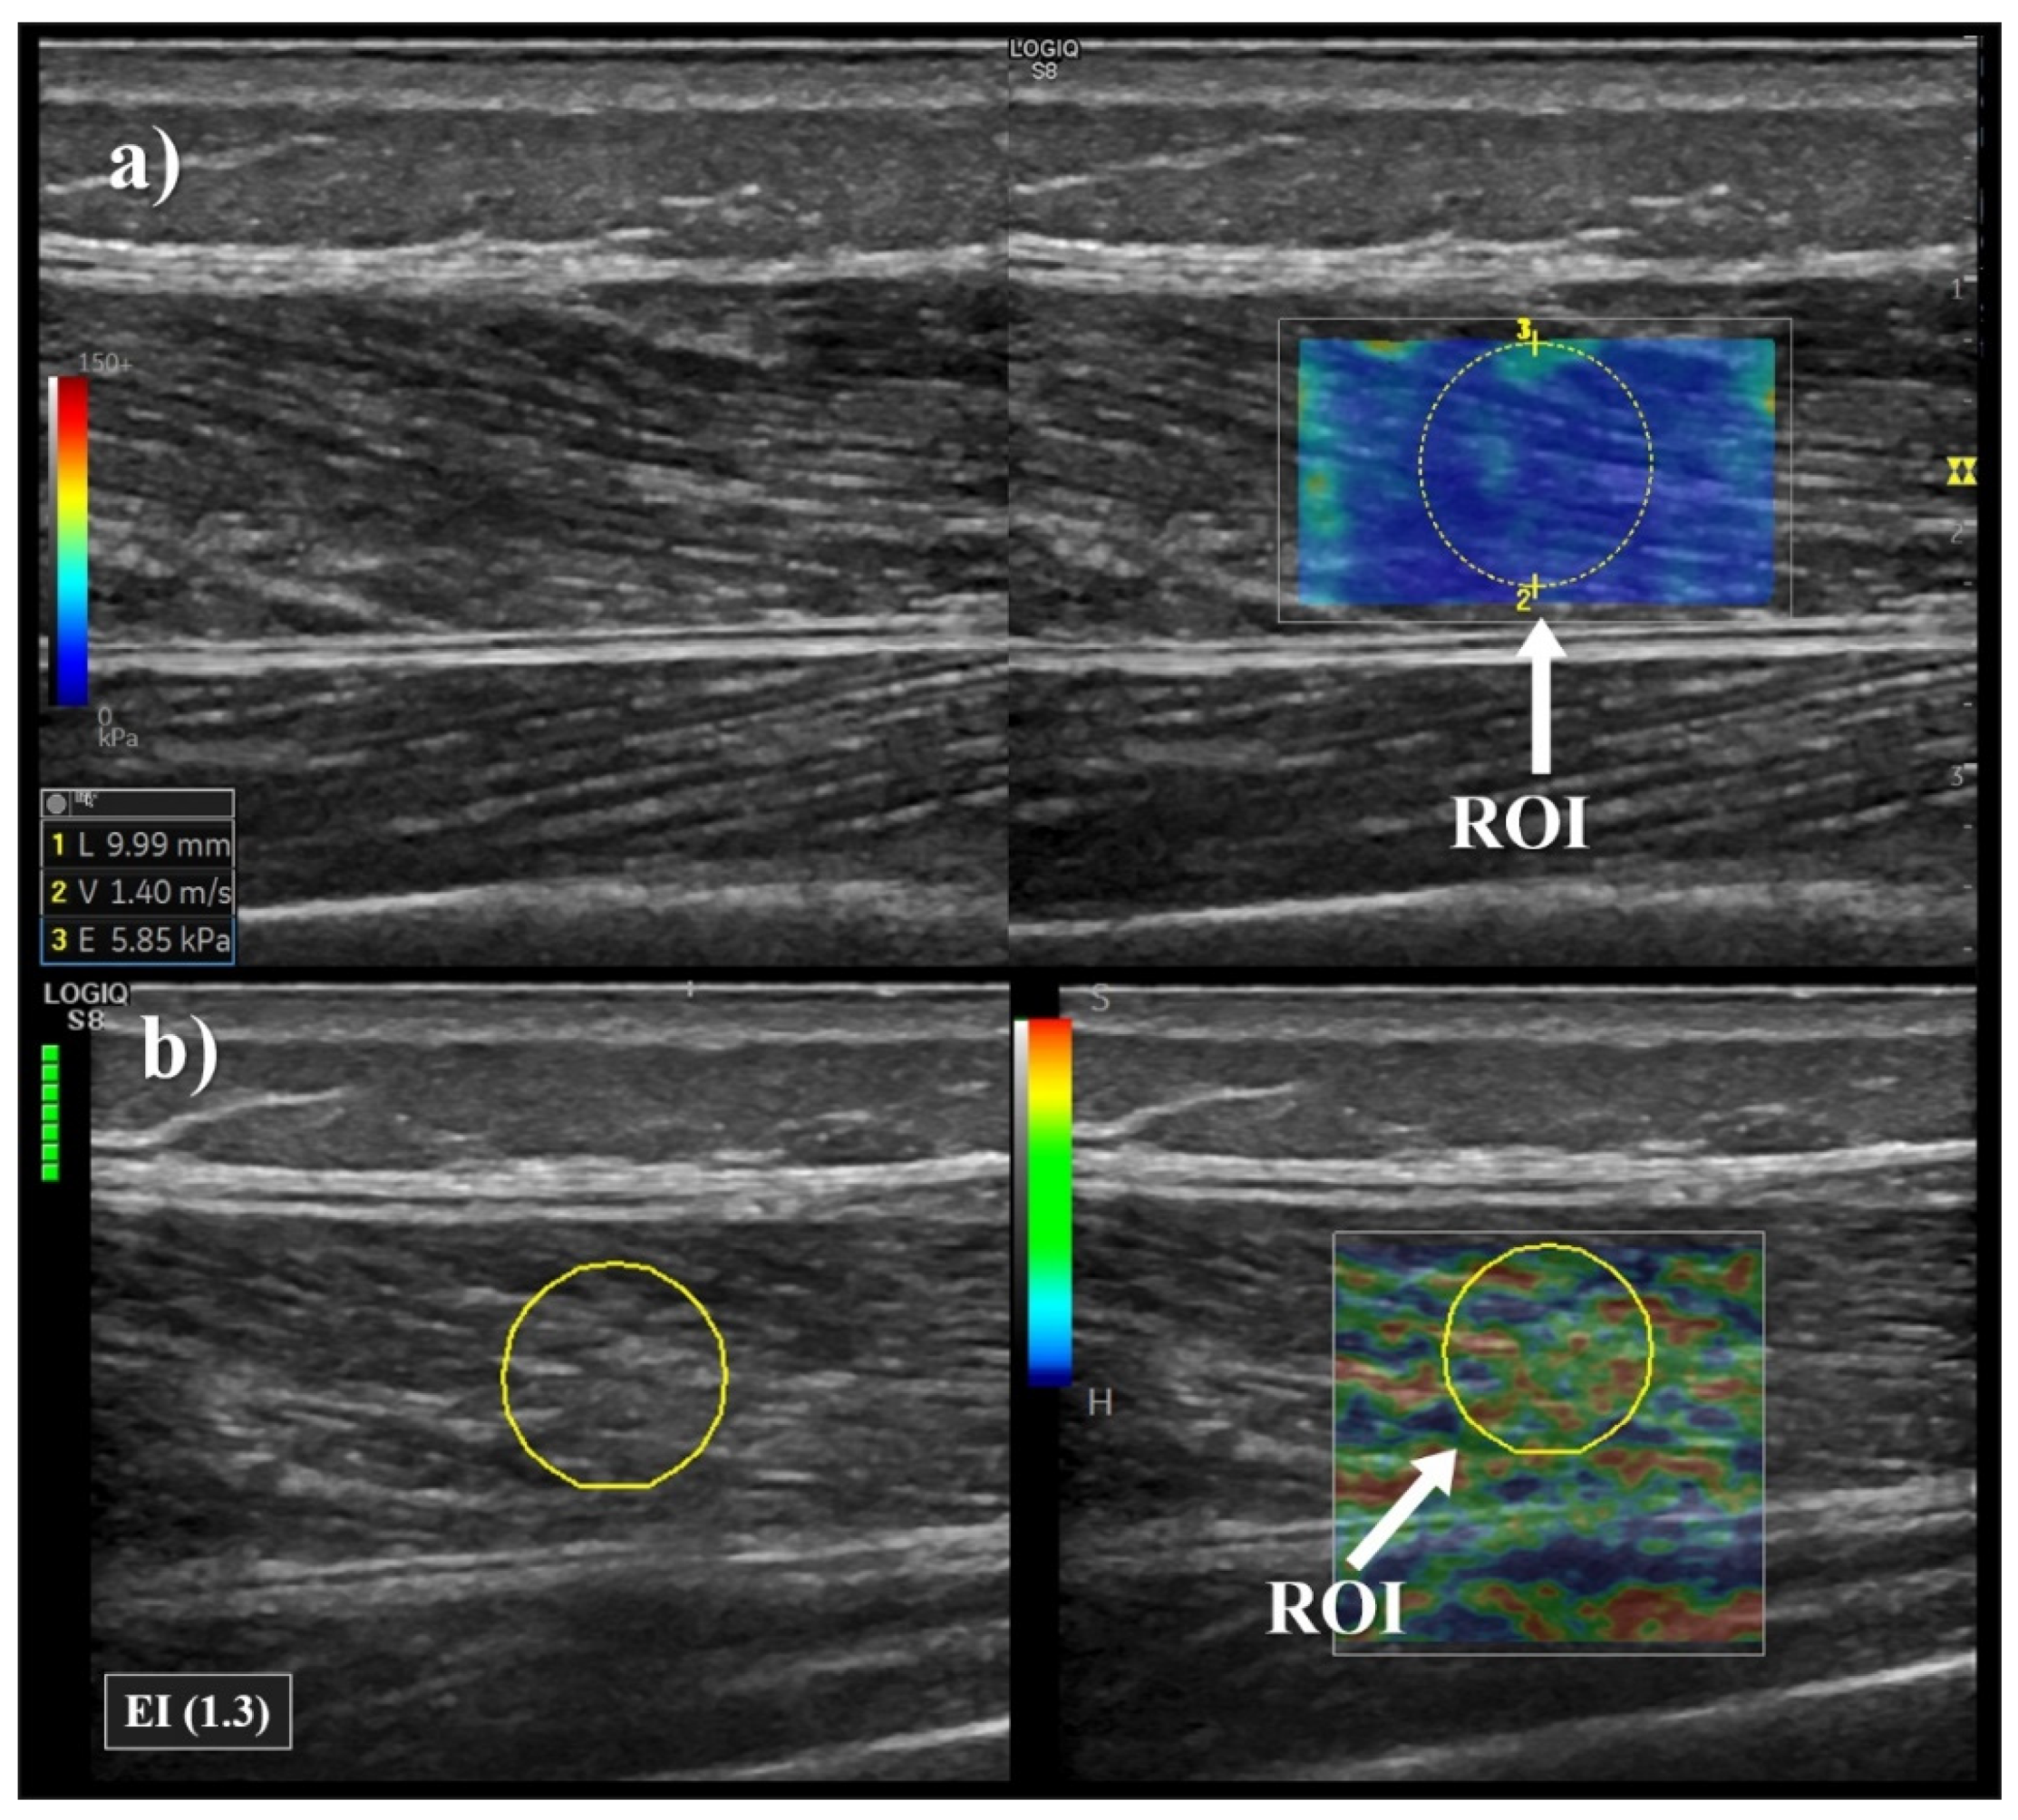

2.4. Elastography Measurements